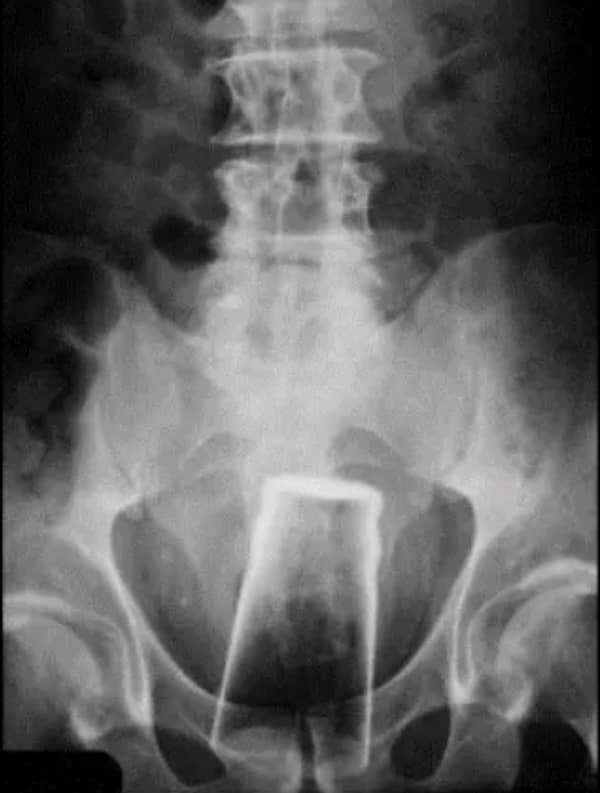

I used to think that nothing could surprise me anymore—until I stumbled upon some weird x-ray photos that made me reconsider my stance on human ingenuity (or lack thereof). Apparently, some people have a knack for getting objects lodged where they absolutely shouldn’t be. If you’ve ever wondered how not to use everyday items, these images might provide some unintended guidance.

This collection showcases 31 bizarre x-ray images that defy logic and anatomy textbooks alike. Each photo reveals unexpected objects making cameo appearances inside the human body, turning medical imaging into a gallery of the absurd. From common household items inexplicably found in unusual places to anomalies that would leave even seasoned doctors scratching their heads, these images offer a perplexing glimpse into the more “creative” side of medical emergencies. They highlight the intersection of curiosity, misadventure, and perhaps a dash of poor decision-making, all captured through the lens of radiology.